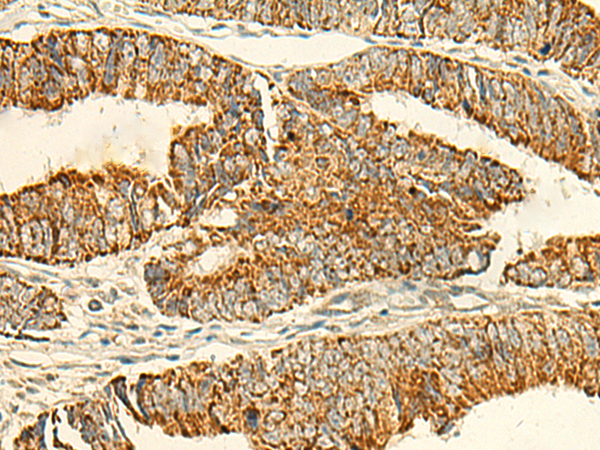

IHC positive control: |

Human tonsil and Human colorectal cancer |

IHC Recommend dilution: |

50-300 |